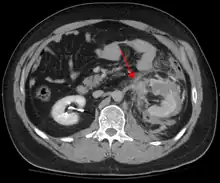

Blunt abdominal trauma

Blunt abdominal trauma (BAT) represents 75% of all blunt trauma and is the most common example of this injury.[3] 75% of BAT occurs in motor vehicle crashes,[4] in which rapid deceleration may propel the driver into the steering wheel, dashboard, or seatbelt,[5] causing contusions in less serious cases, or rupture of internal organs from briefly increased intraluminal pressure in the more serious, depending on the force applied. Initially, there may be few indications that serious internal abdominal injury has occurred, making assessment more challenging and requiring a high degree of clinical suspicion.[6]

When blunt abdominal trauma is complicated by 'internal injury,' the liver and spleen (see blunt splenic trauma) are most frequently involved, followed by the small intestine.[8]

In most settings, the initial evaluation and stabilization of traumatic injury follows the same general principles of identifying and treating immediately life-threatening injuries. In the US, the American College of Surgeons publishes the Advanced Trauma Life Support guidelines, which provide a step-by-step approach to the initial assessment, stabilization, diagnostic reasoning, and treatment of traumatic injuries that codifies this general principle.[8] The assessment typically begins by ensuring that the subject's airway is open and competent, that breathing is unlabored, and that circulation—i.e. pulses that can be felt—is present. This is sometimes described as the "A, B, C's"—Airway, Breathing, and Circulation—and is the first step in any resuscitation or triage. Then, the history of the accident or injury is amplified with any medical, dietary (timing of last oral intake) and history, from whatever sources such as family, friends, previous treating physicians that might be available. This method is sometimes given the mnemonic "SAMPLE". The amount of time spent on diagnosis should be minimized and expedited by a combination of clinical assessment and appropriate use of technology,[33] such as diagnostic peritoneal lavage (DPL), or bedside ultrasound examination (FAST)[34] before proceeding to laparotomy if required. If time and the patient's stability permits, CT examination may be carried out if available.[35] Its advantages include superior definition of the injury, leading to grading of the injury and sometimes the confidence to avoid or postpone surgery. Its disadvantages include the time taken to acquire images, although this gets shorter with each generation of scanners, and the removal of the patient from the immediate view of the emergency or surgical staff. Many providers use the aid of an algorithm such as the ATLS guidelines to determine which images to obtain following the initial assessment. These algorithms take into account the mechanism of injury, physical examination, and patient's vital signs to determine whether patients should have imaging or proceed directly to surgery.[8]